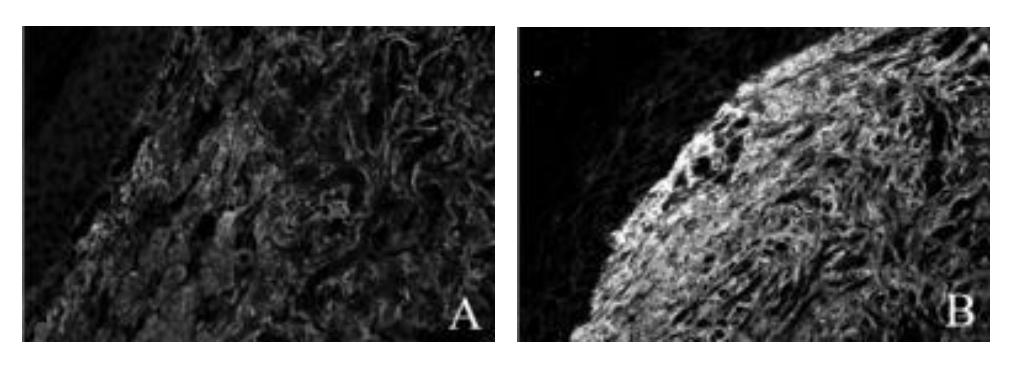

정상 피부 (a)와 scleroderma 피부 (b)에서 Fibronectin 침착. Scleroderma에서 fibronectin 침착이 증가한 것을 볼 수 있다.

정상 피부에 비해 scleroderma 피부에서 fibronectin 침착이 증가한다.